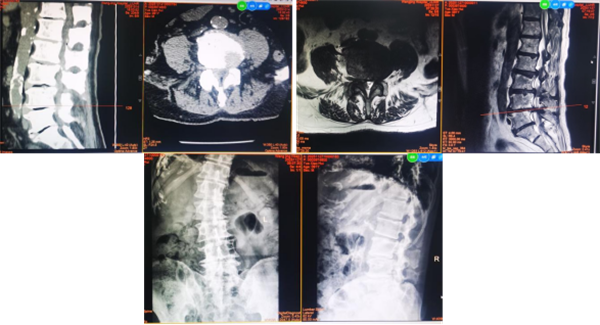

入院时影像资料

1. 完整评估,明确诊断。腰椎 CT显示:椎管严重的骨性狭窄。MRI示:多节段腰椎管狭窄合并间盘突出。动态位 X 片示:退变性脊柱侧凸。经科室充分讨论,诊断为多节段重度腰椎管狭窄合并间盘突出,退变性脊柱侧凸症。